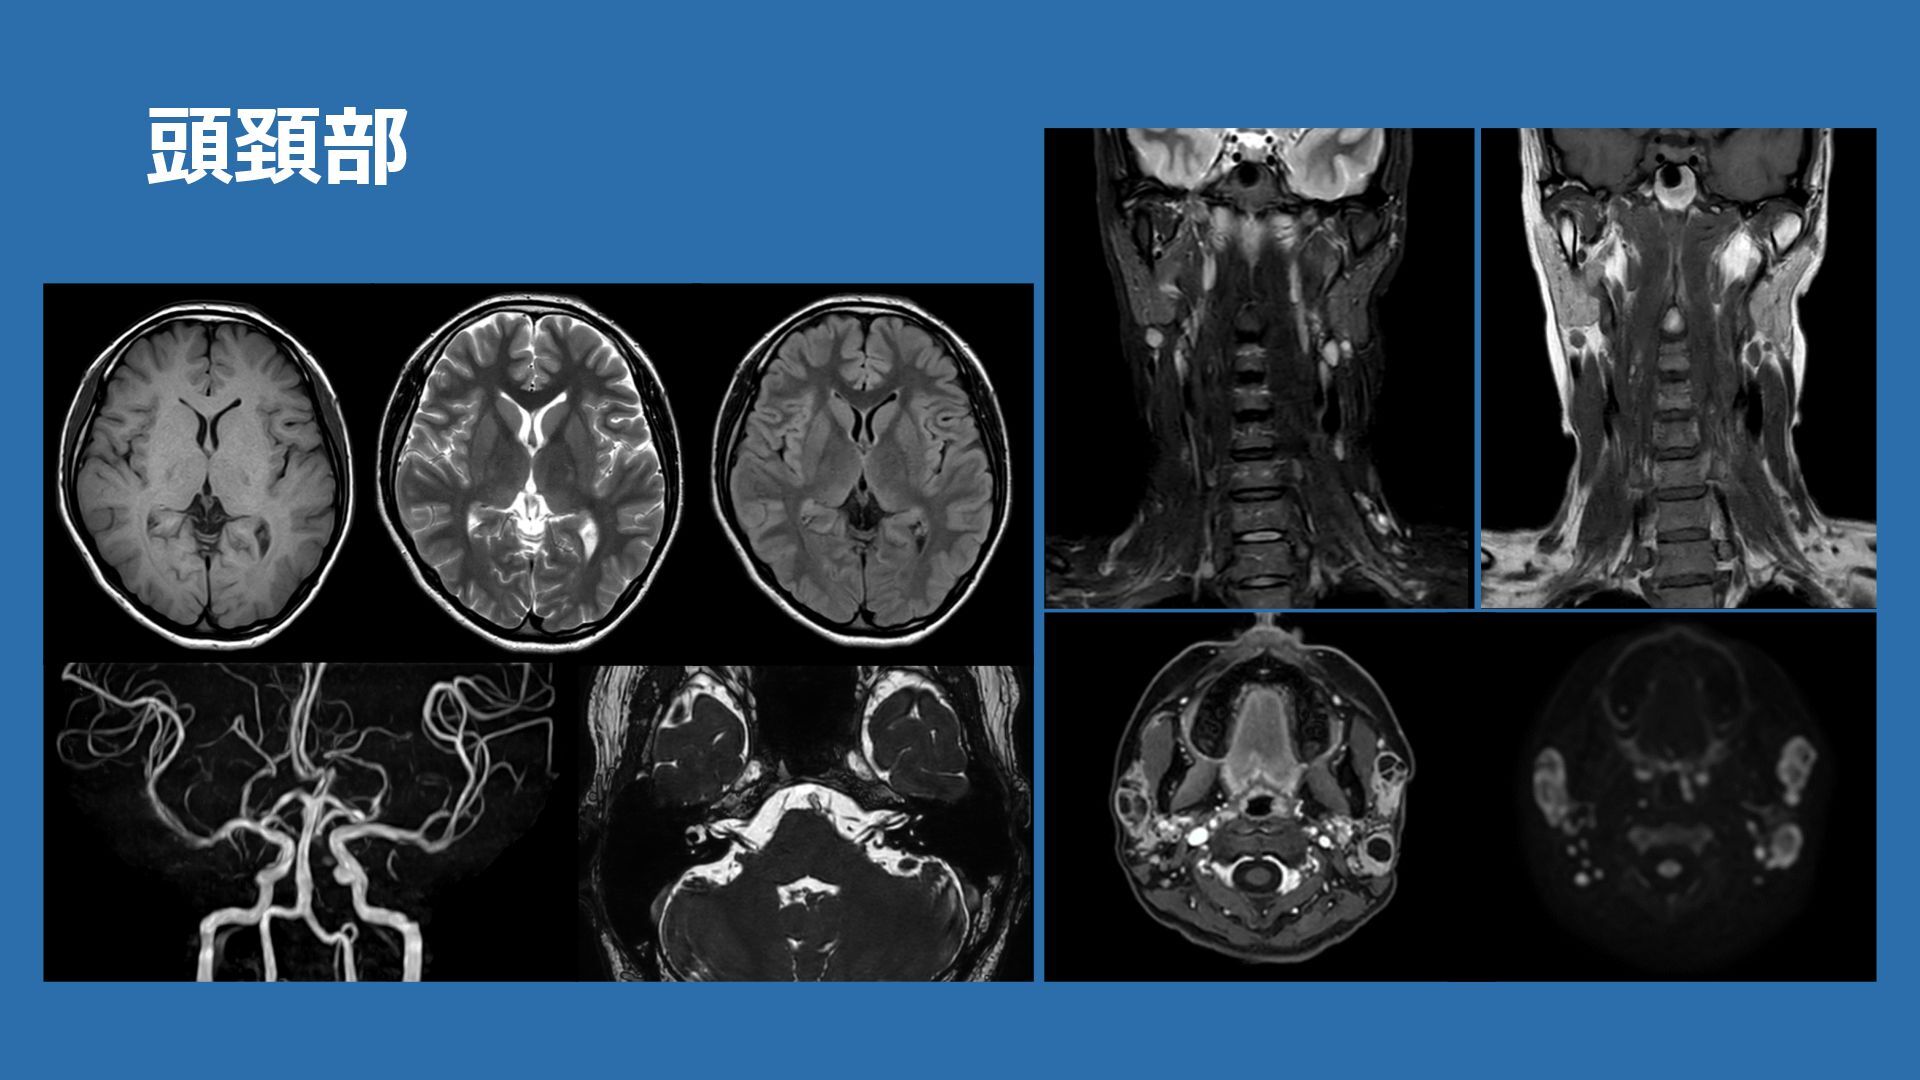

頭頚部